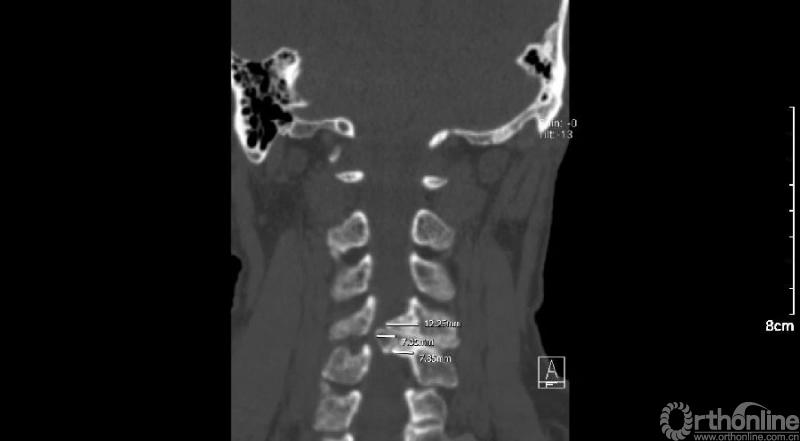

入院查体患者四肢肌张力高,双侧hoffman阳性。CT及MRI检查提示C4/5左侧关节突内缘有一巨大骨块(15mm*16mm),相应节段椎管严重狭窄。椎管内骨块的前端还有一游离骨块。

影像学资料